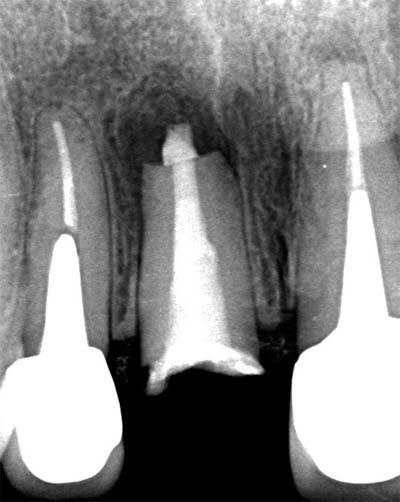

根尖封鎖の比較

![]() |

| MTA根充前 | MTA根充後 |

MTA / バイオセラミックによる3次元根尖封鎖

根の先端に行う“根尖封鎖”は、治療の成否を左右する超重要工程です。

| MTA充填前 | MTA充填後 |

MTA・バイオセラミックは、

- 封鎖性が高い

- 硬化後の安定性が良い

- 骨の治癒を促す

- 組織親和性が高い

- 再感染が起きにくい

という特徴があり、現代の根管治療のゴールドスタンダードといえます。

Torabinejad(1995)もMTAは従来材料より漏洩が極めて少ないと報告しています: